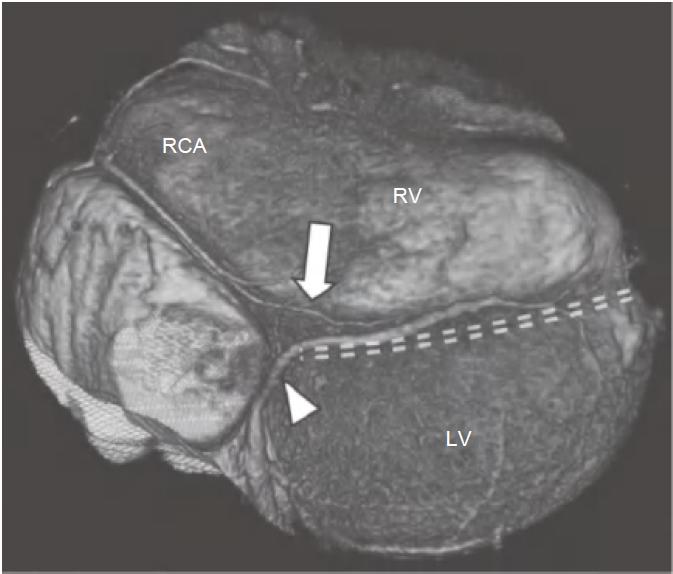

通常,RCA自右冠窦前方发出后在右房室间沟(RAVG)内向前然后向下走行,到达心脏的后方(图13-3及图13-4)。

图13-3 RCA(白箭)起自主动脉的前部,并沿RAVG(黑箭)走行。图中还可见位于前室间沟内(箭头)的LAD

AO.主动脉;PA.肺动脉;RA.右心房;RV.右心室;LV.左心室

图13-4 RCA优势型,RCA绕过右心缘,在RAVG的下方发出后降支(箭),并走行于后室间沟(虚线)。心中静脉(箭头)也在后室间沟内走行

RCA.右冠状动脉;RV.右心室;LV.左心室